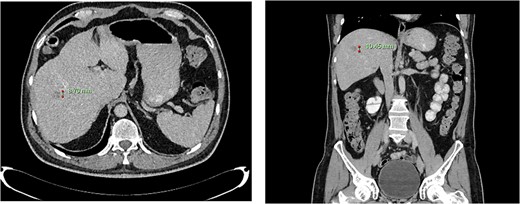

Computed tomography dated 25 September 2012 of the abdomen and pelvis measuring 18.65 mm (anterior–posterior) lesion at liver segment 5/6 in axial (left) and coronal (right) view.

Computed tomography dated 15 January 2013 of the abdomen and pelvis measuring 10.50 mm (anterior–posterior) lesion at liver segment 5/6 in axial (left) and coronal (right) view.

Subsequent surveillance imaging including magnetic resonance imaging and CT scans demonstrated gradual reduction and eventual complete resolution of the liver metastases (refer to Figs 1–4). Furthermore, routine colonoscopy and a positron emission tomography (PET) scan revealed no evidence of locoregional cancer recurrence nor distant metastatic disease present; essentially rendering the patient cured from an initial diagnosis of metastatic rectal cancer. It has been at least a decade since his initial diagnosis and the patient remains in remission.

Computed tomography dated 12 March 2013 of the abdomen and pelvis measuring 8.70 mm (anterior–posterior) lesion at liver segment 5/6 in axial (left) and coronal (right) view.